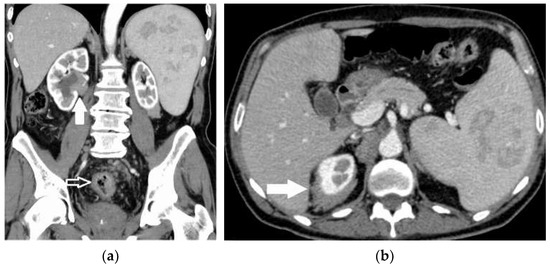

2.5. Hematoma and Abscess

2.6. Infarcts

2.7. Solid Lesions